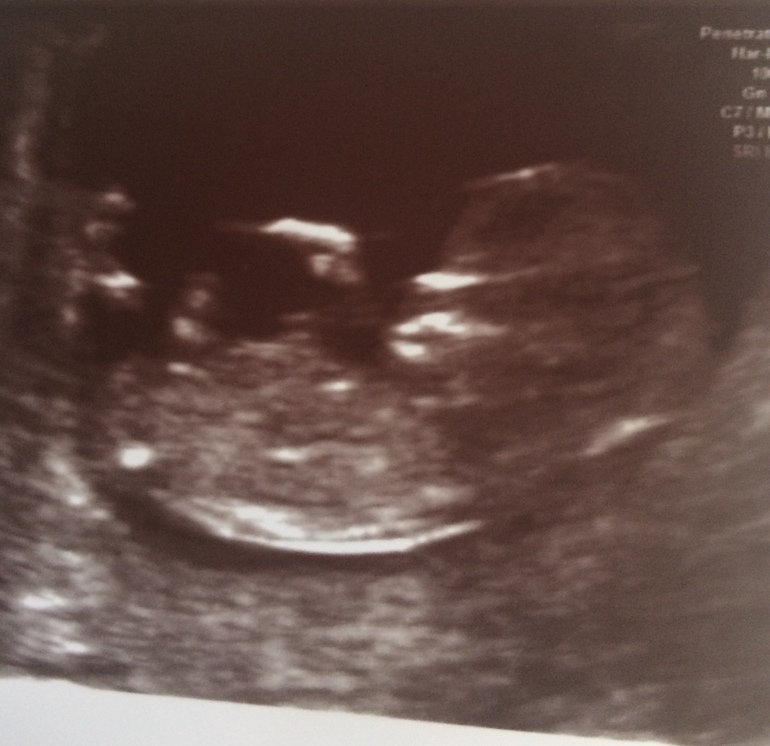

Наши будни, наши неделькиДевчули,привет.🍓 мои новости,позавчера были с мужем на скрининге,на тот момент срок 11 нед и 3 дня был. Вообще скрининг запланирован у меня на 25.06,но у меня шило в одном месте,я все переживала как малыш,просто на узи не было смысла идти,решила на скрининг. Конечно я ещё и 25 пойду. Все что позавчера увидели,все хорошо сказали (тьфу тьфу тьфу не сглазить своё счастье🙏🏻). Малыш плавал,махал ручками и ножками,я счастлива... Счастлива на столько,что боюсь сглазить. Никому ещё не говорили,ни на работе,ни друзьям,ни родным. Моя бы воля,так вообще никому бы и не рассказывала.😂 Пока в ожидании 25 числа,я молюсь чтоб все будет хорошо,и малыш здоровый,и благополучно родится в срок. Вопрос при живот,толи я сильно переела сладкое,потому что мне хочется сладкое и фрукты постоянно. Толи живот начинает не от булочек появляться.😁 в весе прибавка на 500 гр,но живот значительно вырос. Сказали прикреплён к передней стенки. Хочу посмотреть ваши животики на этом сроке,а вы посмотрите какой сладенького малыша нам показали позавчера.😍 кстати,токсикоз у меня сейчас сильней,чем на 8 недели например. Почти каждое утро 🤢